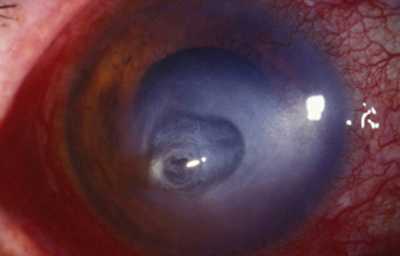

En su evolución se observará aumento del edema, agrandamiento y coalescencia de los infiltrados formando un anillo, (Figura 9, 10 y 11) que progresa hacia la formación de un absceso (Figura 12, 13 y 14), queratolisis superficial, adelgazamiento y perforación corneal (Figura 15 y 16).

La vascularización y el hipopion son poco frecuentes en los estadios tempranos de la queratitis. Con el tiempo, en los estados avanzados de invasión estromal, aparecen vasos estromales (Figura 17)

Es llamativa la asociación de los infiltrados corneales a dolor desmedidamente intenso, frecuentemente más notable por la noche. Este síntoma no está siempre presente.

En los estados avanzados con abscesificación y queratolisis, se enmascara el cuadro corneal, ocultando las características clínicas típicas de la queratitis por Acanthamoeba. (Fig 18)